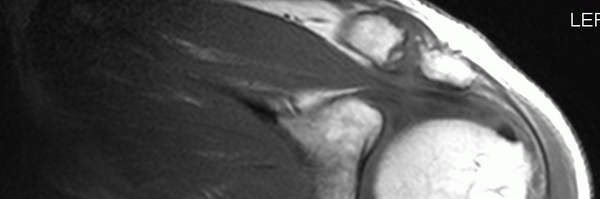

Interesting work by J Plante, Joe Kucksdorf & Jon Ruzich - maladaptive imaging beliefs were associated w poorer outcomes compared to healthy beliefs in patients w musculoskeletal pain @jlyoung2 @BellinCollegePT

jospt.org

OBJECTIVE: To determine if maladaptive imaging beliefs correlated with, and predicted pain interference and physical function outcomes in people with musculoskeletal pain disorders. DESIGN: A...